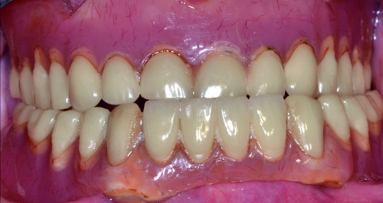

Following the bonding, the restoration is steam cleaned to remove any residue. The final restoration (Fig. 22) is now ready to be inserted, approximately 2 hours after the patient arrived in the practice (Fig. 23).

The restoration is finally torqued down to 25 Ncm. Following this, occlusion is rechecked, but no adjustment is required at this stage following the try-in adjustments. PTFE is placed in the access cavity and the access hole filled with opacious composite (OMC Venus Pearl) and stained with Venus tints (Figs. 24–26).

In conclusion, as you can see in the final result (Figs. 27–29) an aesthetic, biologically designed and durable restoration has been fabricated. The patient has been delivered the final restoration in a single visit without the need for traditional analogue impressions.